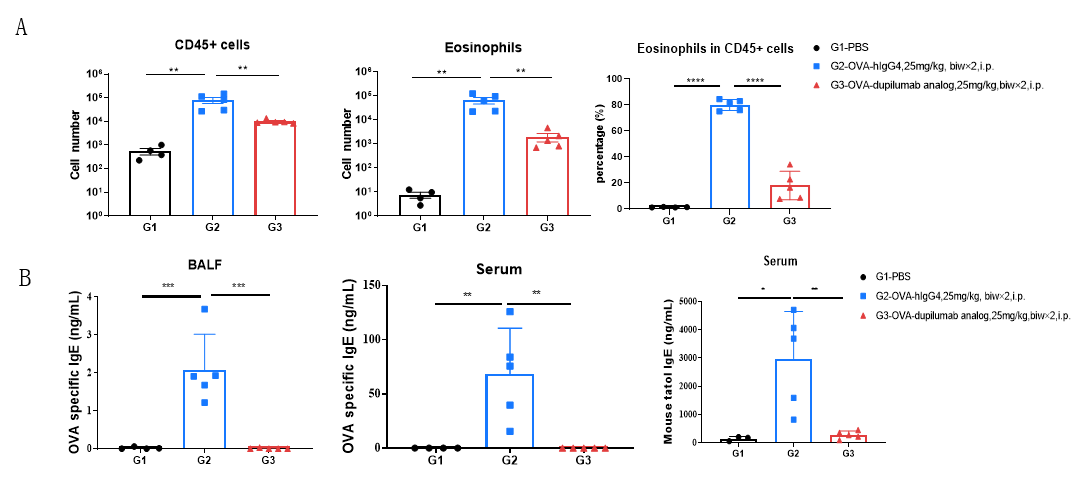

Analysis of immune cells in BALF by FACS and IgE production in serum. BALF immune cells were isolated from B-hIL4/hIL4RA mice (n=4 or n=5). The number and proportion of eosinophils were analyzed by flow cytometry under the treatment of PBS/dupilumab (in house). After treatment of dupilumab (in house), the number of CD45+ cells and eosinophils were much lower than the positive control in homozygous B-hIL4/hIL4RA mice. Serum was collected at the study endpoint. IgE levels responded to OVA-specific antibody and total IgE levels were analyzed. The results show that the levels of IgE in mice treated with dupilumab (in house) is much lower than that in untreated mice.

Analysis of immune cells in BALF by FACS and IgE production in serum. BALF immune cells were isolated from B-hIL4/hIL4RA mice. The number and proportion of eosinophils were analyzed by flow cytometry under the treatment of PBS/dupilumab (in house). After treatment of dupilumab (in house), the number of CD45+ cells and eosinophils were much lower than the positive control in homozygous B-hIL4/hIL4RA mice. Serum was collected at the study endpoint. IgE levels were analyzed. The results show that the levels of IgE in mice treated with dupilumab (in house) is much lower than that in untreated mice.